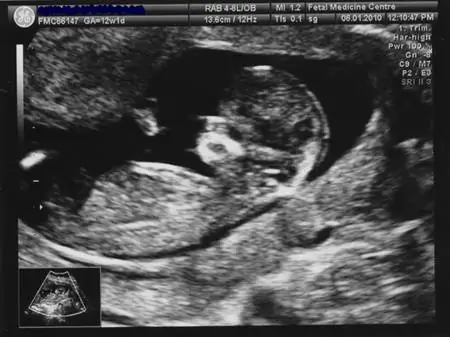

13. неделя

В настоящее время почти во всех развитых странах мира, где предоставляется организованный уход за беременными, в конце первого триместра или в начале второго триместра проводится та или иная форма скрининга на наличие аномалий. В Великобритании, где я живу, так называемый комбинированный тест дает самые точные результаты среди безрисковых и неинвазивных тестов, выявляющих хромосомные аномалии. Инвазивные обследования никогда не проводятся рутинно (даже в возрасте старше 35 лет), за исключением случаев, когда это серьезно оправдано. Комбинированный тест учитывает возраст матери, уровень двух гормонов в крови и размер вод на затылке, который измеряют с помощью УЗИ. Во время осмотра также изучается анатомия, органы и размеры ребенка. Конечным результатом является не определенный ответ на вопрос о наличии расстройства, а число, показывающее вероятность расстройства у данной будущей матери.

Перед анализом крови я подписал форму, в которой указывалось, что я даю согласие профессору на использование результатов моего обследования в своих исследованиях и на то, чтобы поделиться ими со всем миром. К тому времени, как я смогла лечь в кабинете УЗИ, я едва могла скрыть свое волнение. Внезапно в голову пришли все мои страхи, я вспомнила сообщения на форуме от мам, у которых на УЗИ в 12 недель не нашли сердцебиение (почему мы всегда помним именно о тех, а не о многих тысячах, где все было хорошо?) это последняя счастливая минута моей беременности? Я дрожащими руками спустила штаны, сонографистка намазала мне живот теплым гелем, начала давить на него пальцем, и я ни разу не дышал. Потом я услышала стук сердца и вдруг наполнилась огромным счастьем. Обследование было тщательным и очень долгим, и врач УЗИ все время комментировал. Он сказал мне, что ему нелегко измерить, потому что моя матка в данный момент находится в спазме, что совершенно нормально и может длиться до 30 минут. Он точно рассказывал мне, на что смотрел и что измерял, и всегда добавлял, что вроде бы все в порядке. Носовая кость, отсутствие которой является зловещим признаком, была хорошо видна. Когда он направил ультразвук на заводь, я проследил за ним неподвижным взглядом и увидел, где находится темная область, которую он измерял. Даже неспециалисту она показалась маленькой, длинной, очень узкой полосой. после измерений зашел профессор, с которым сонограф поделился моими данными. Профессор улыбнулся и пожал мне руку, погладил лицо дочери и сел перед аппаратом. Казалось, он повторял и проверял некоторые измерения, а также все время разговаривал с нами. Хотя он явно в десятитысячный раз поделился с будущей мамой хорошим результатом, я ни на минуту не почувствовала, что рутинна. Он помог мне сесть и показал восходящую кривую на своем экране. «Исходя из его возраста, у него может быть генетическое заболевание», - указал он на кривой. «По УЗИ и анализу крови все», - указал он на противоположную сторону кривой. «Точно как 15-летняя девочка. Раньше ты вел себя как 15-летняя девочка?», - спросила она моего партнера, посмеиваясь. Ребята улыбнулись, я оделся и встал, все еще немного трясясь. Мы получили документ, полный цифр и таблиц, и последнее слово о том, что дальнейшие тесты не рекомендуются, исходя из моего фактора риска.